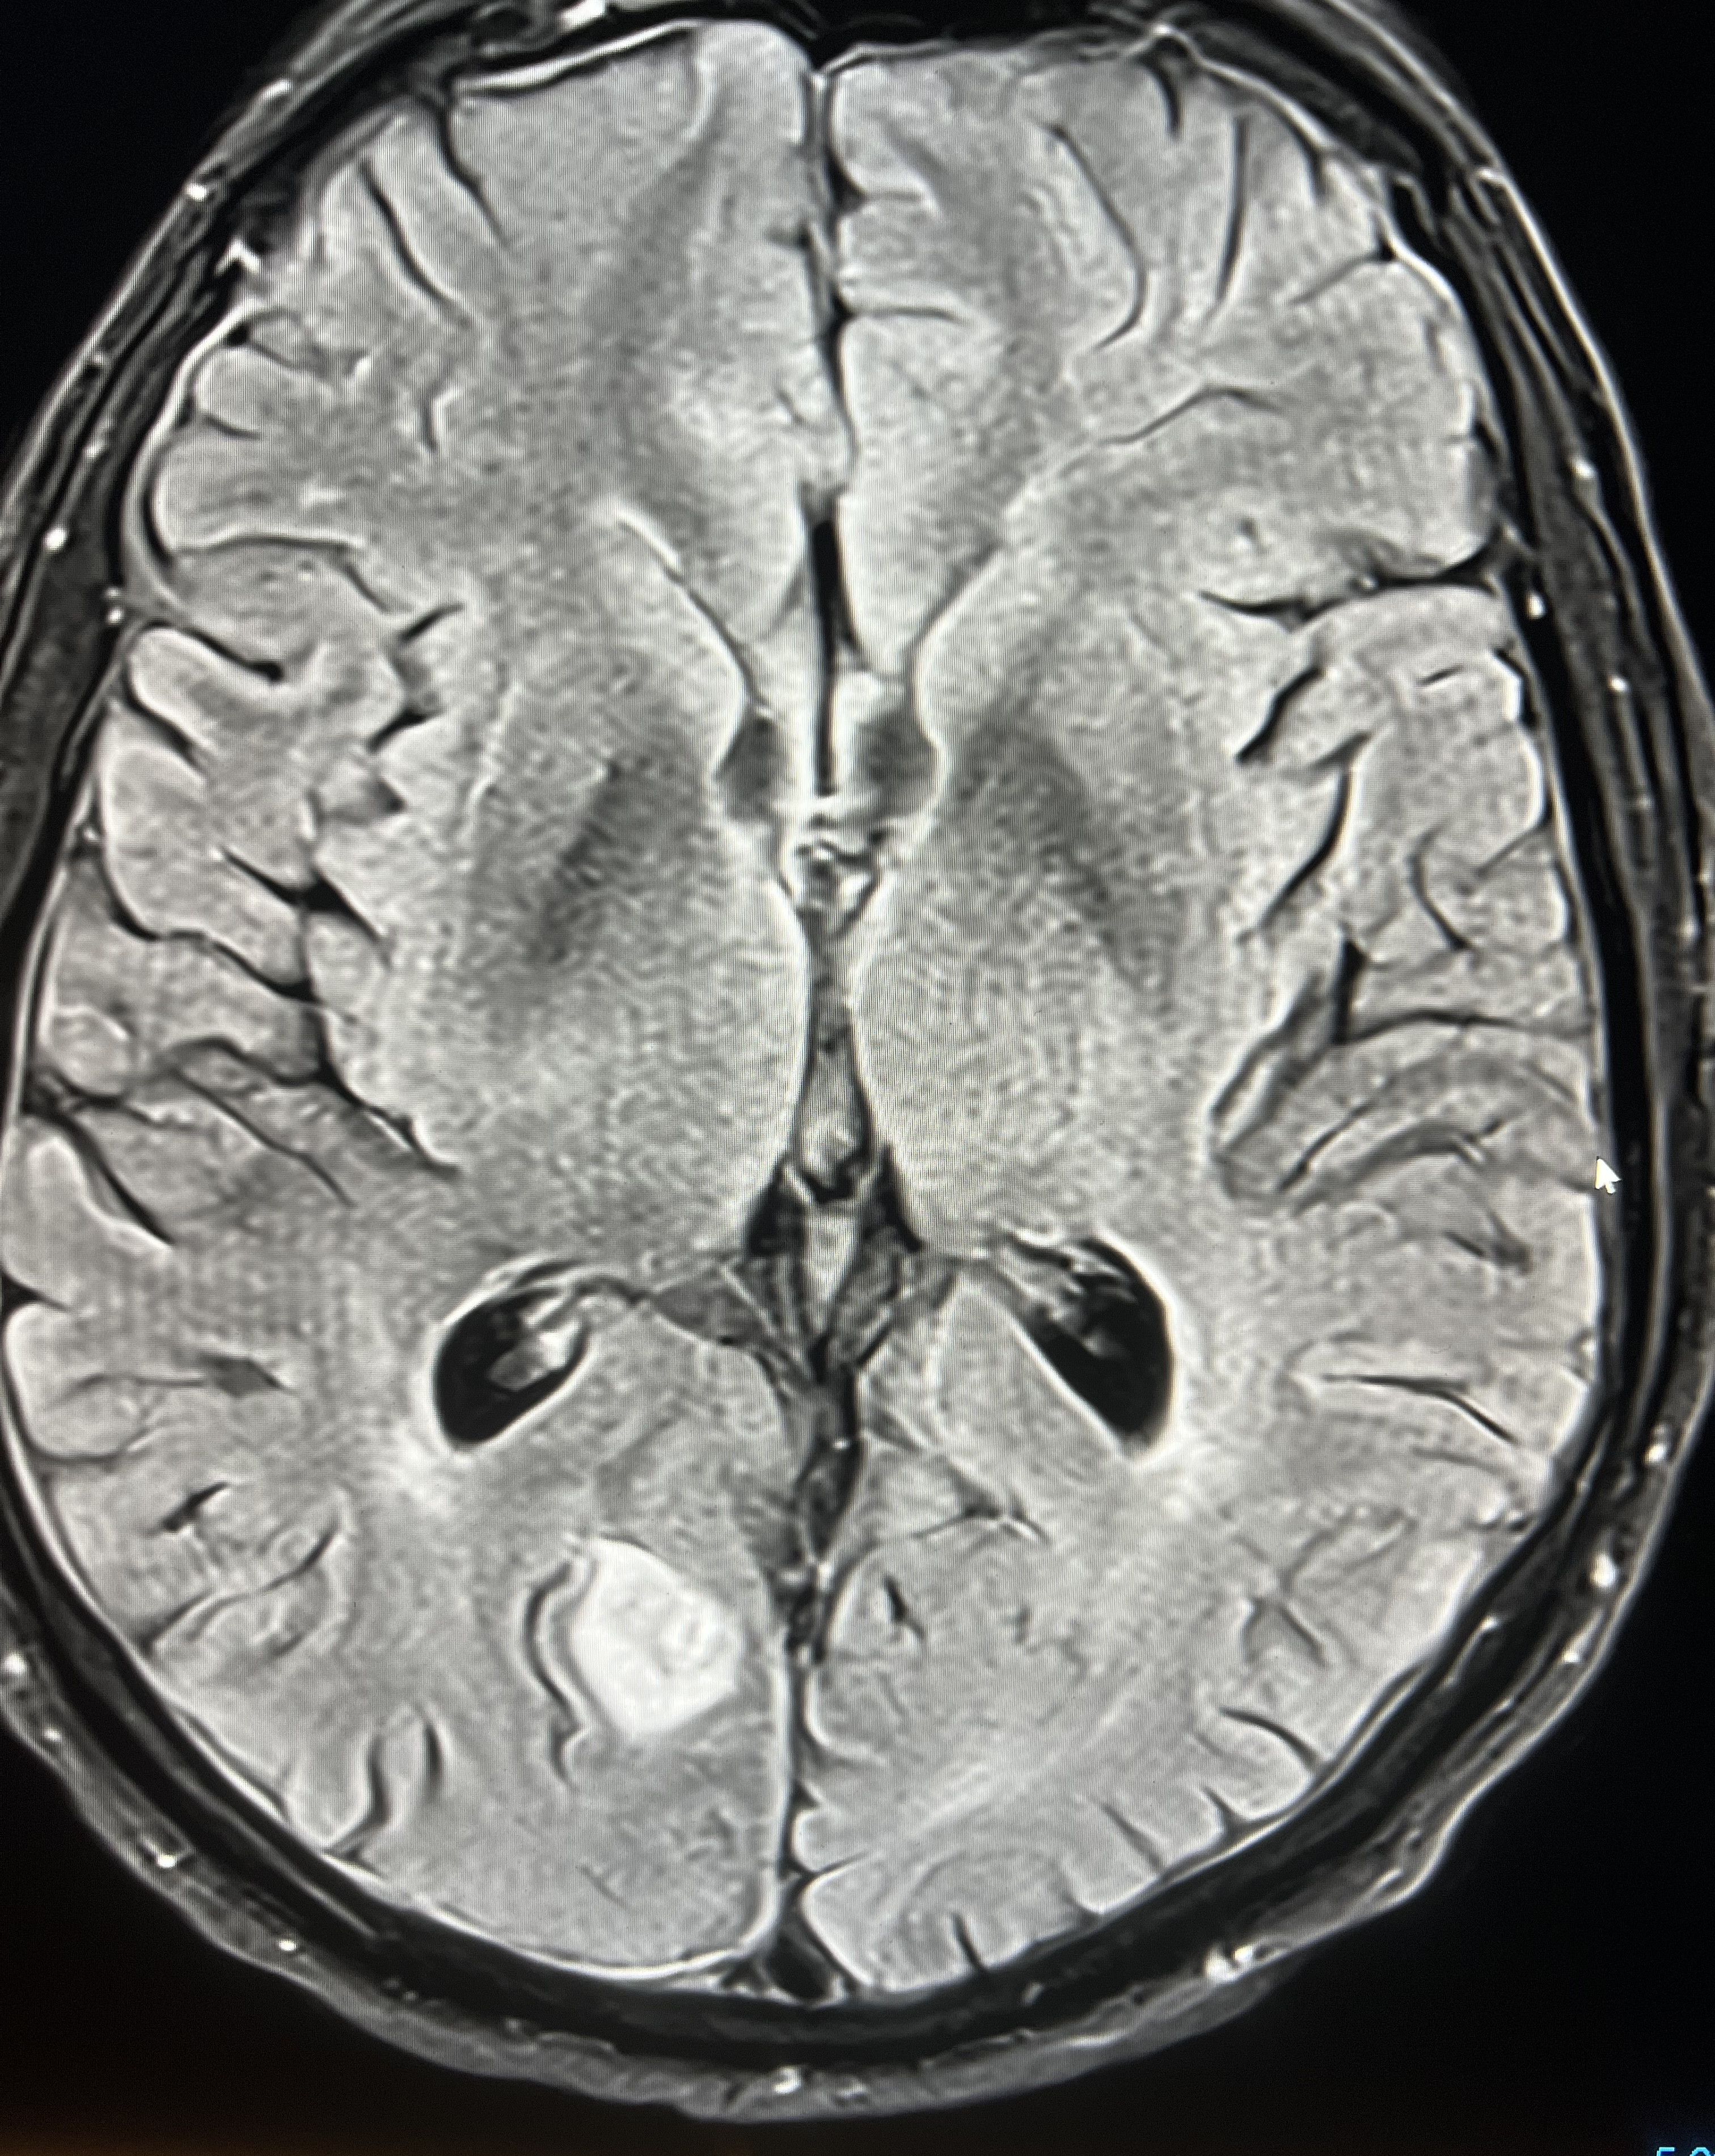

A 77 male presented with a 10 history of visual symptoms following heavy exertion. He described it as an afterimage on his left temporal field eg he would see a person walking past and then see them again a moment later. There was no headache. MRI with contrast showed a right superficial occipital lobe haemorrhagic infarct with mild diffuse meningeal enhancement, related to the haemorrhage. He was treated conservatively with follow up by a neurologist.